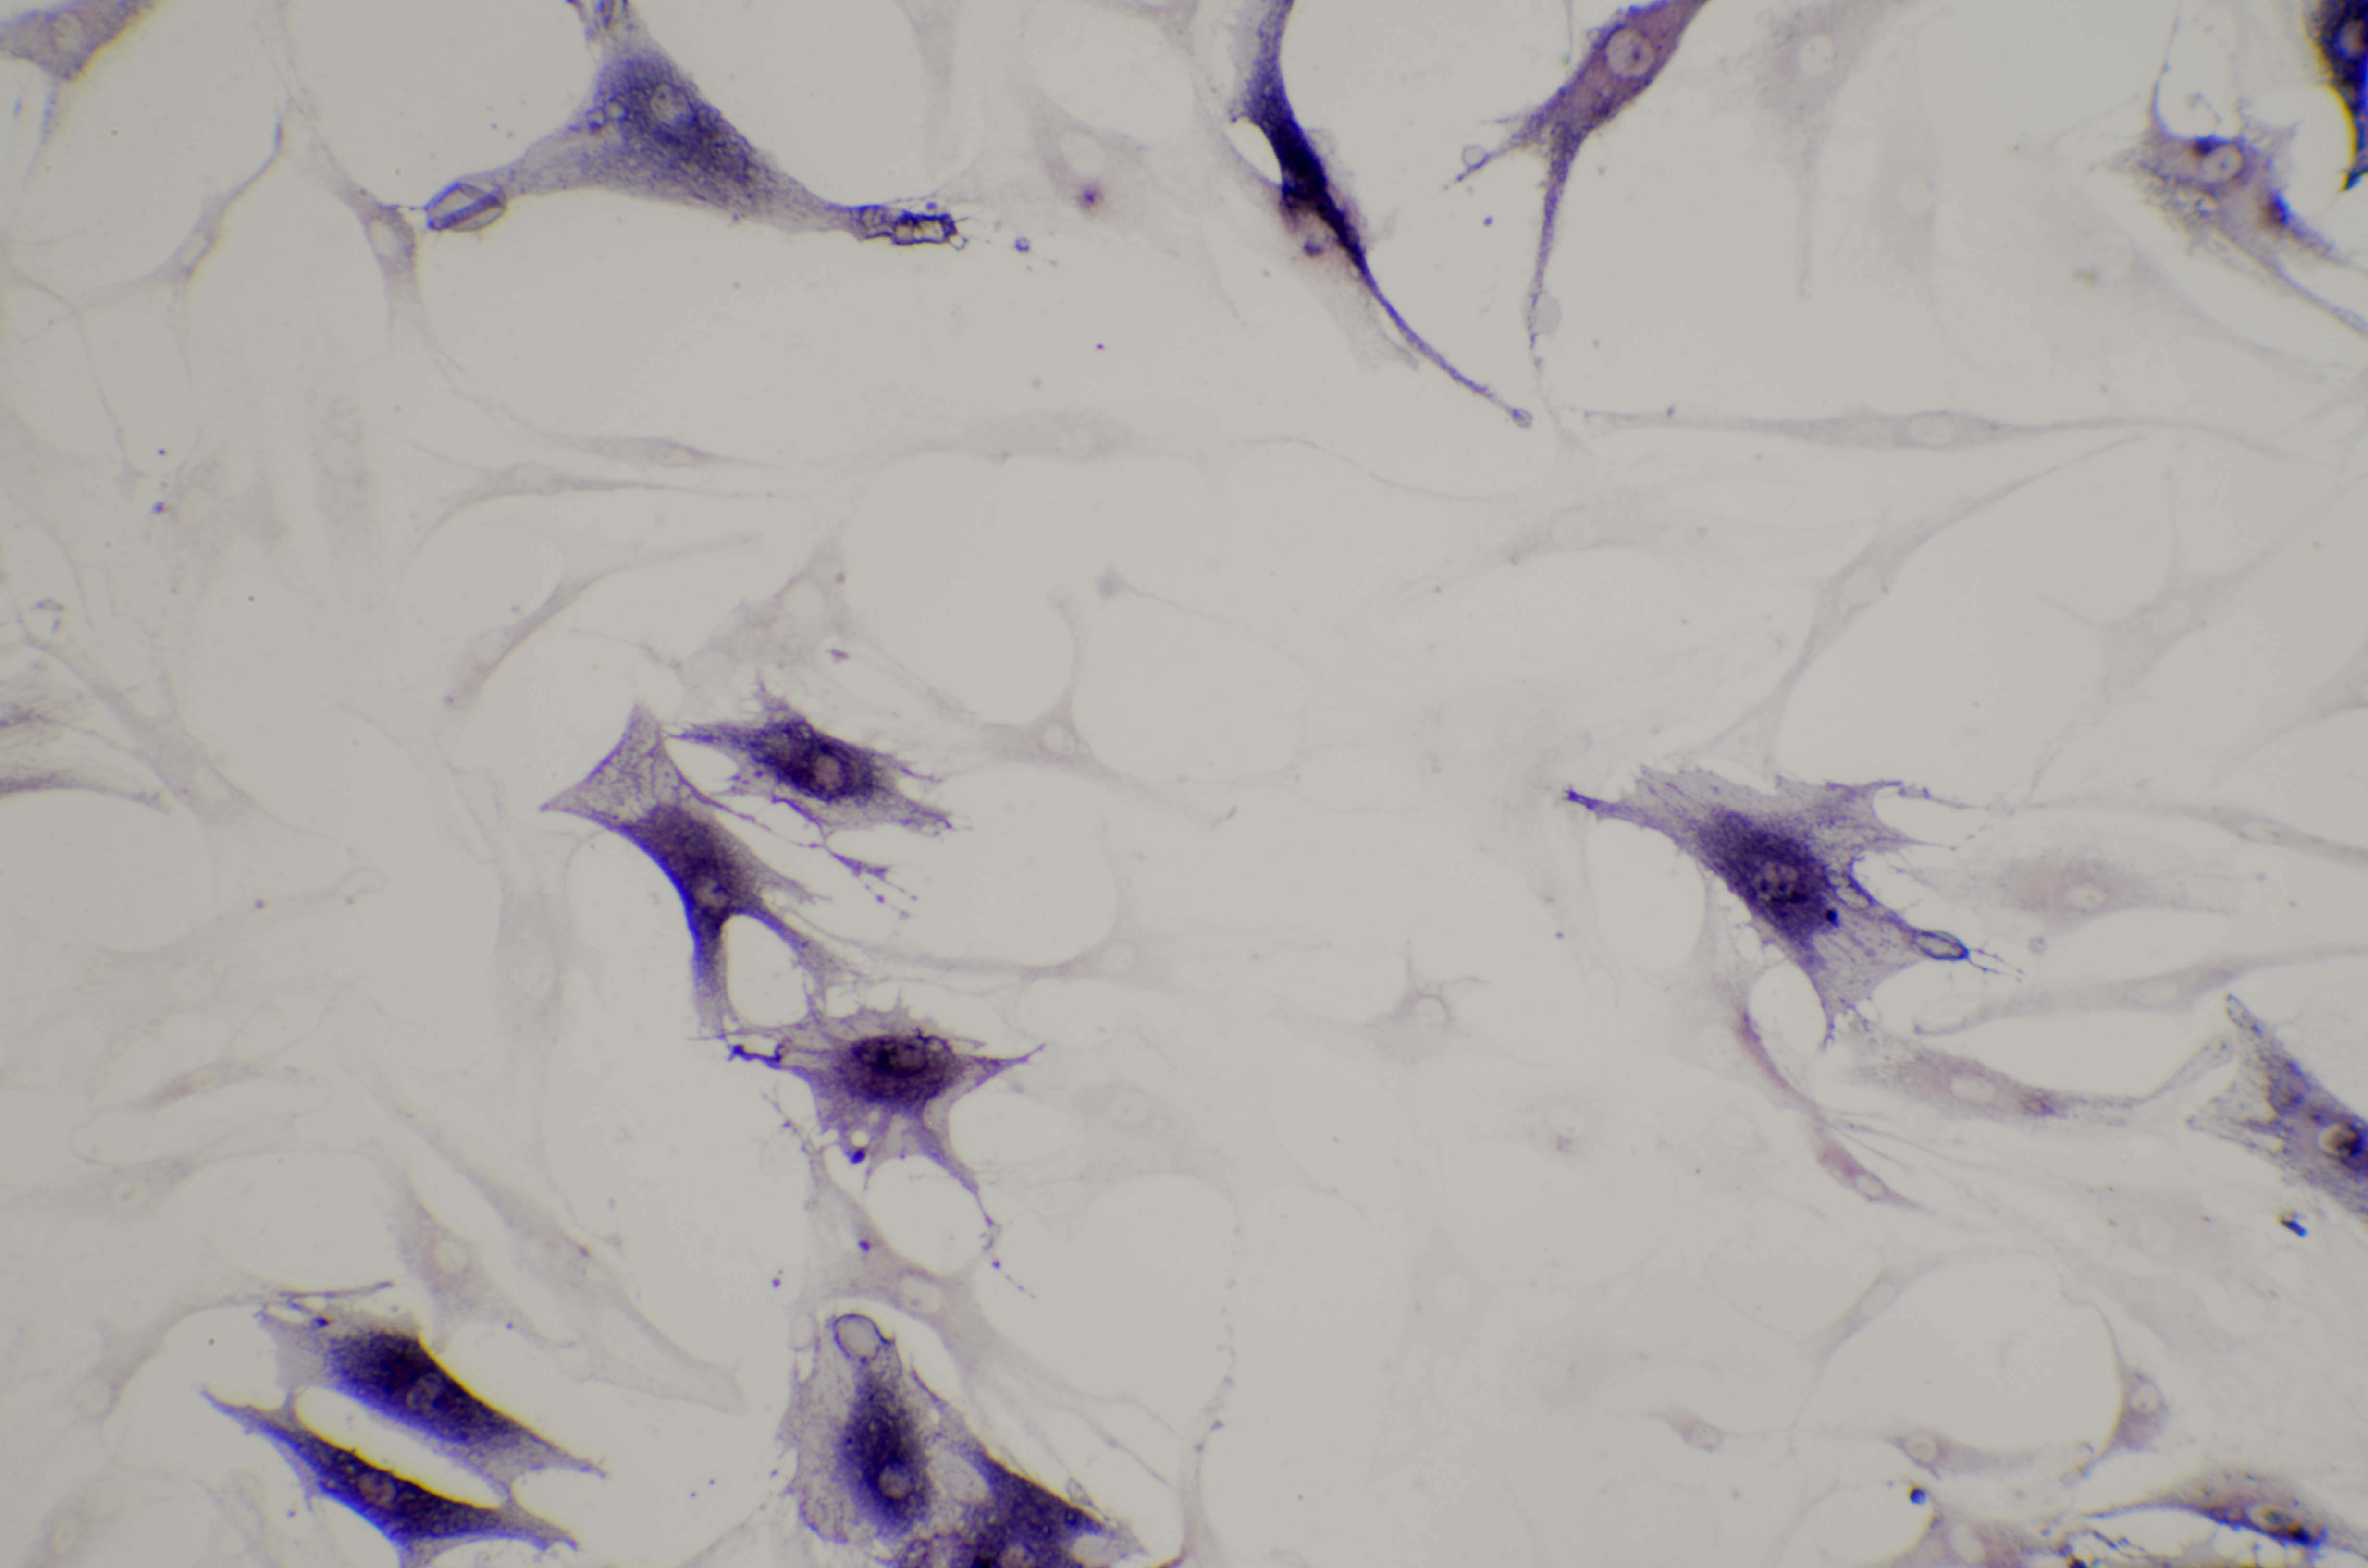

ALP实验